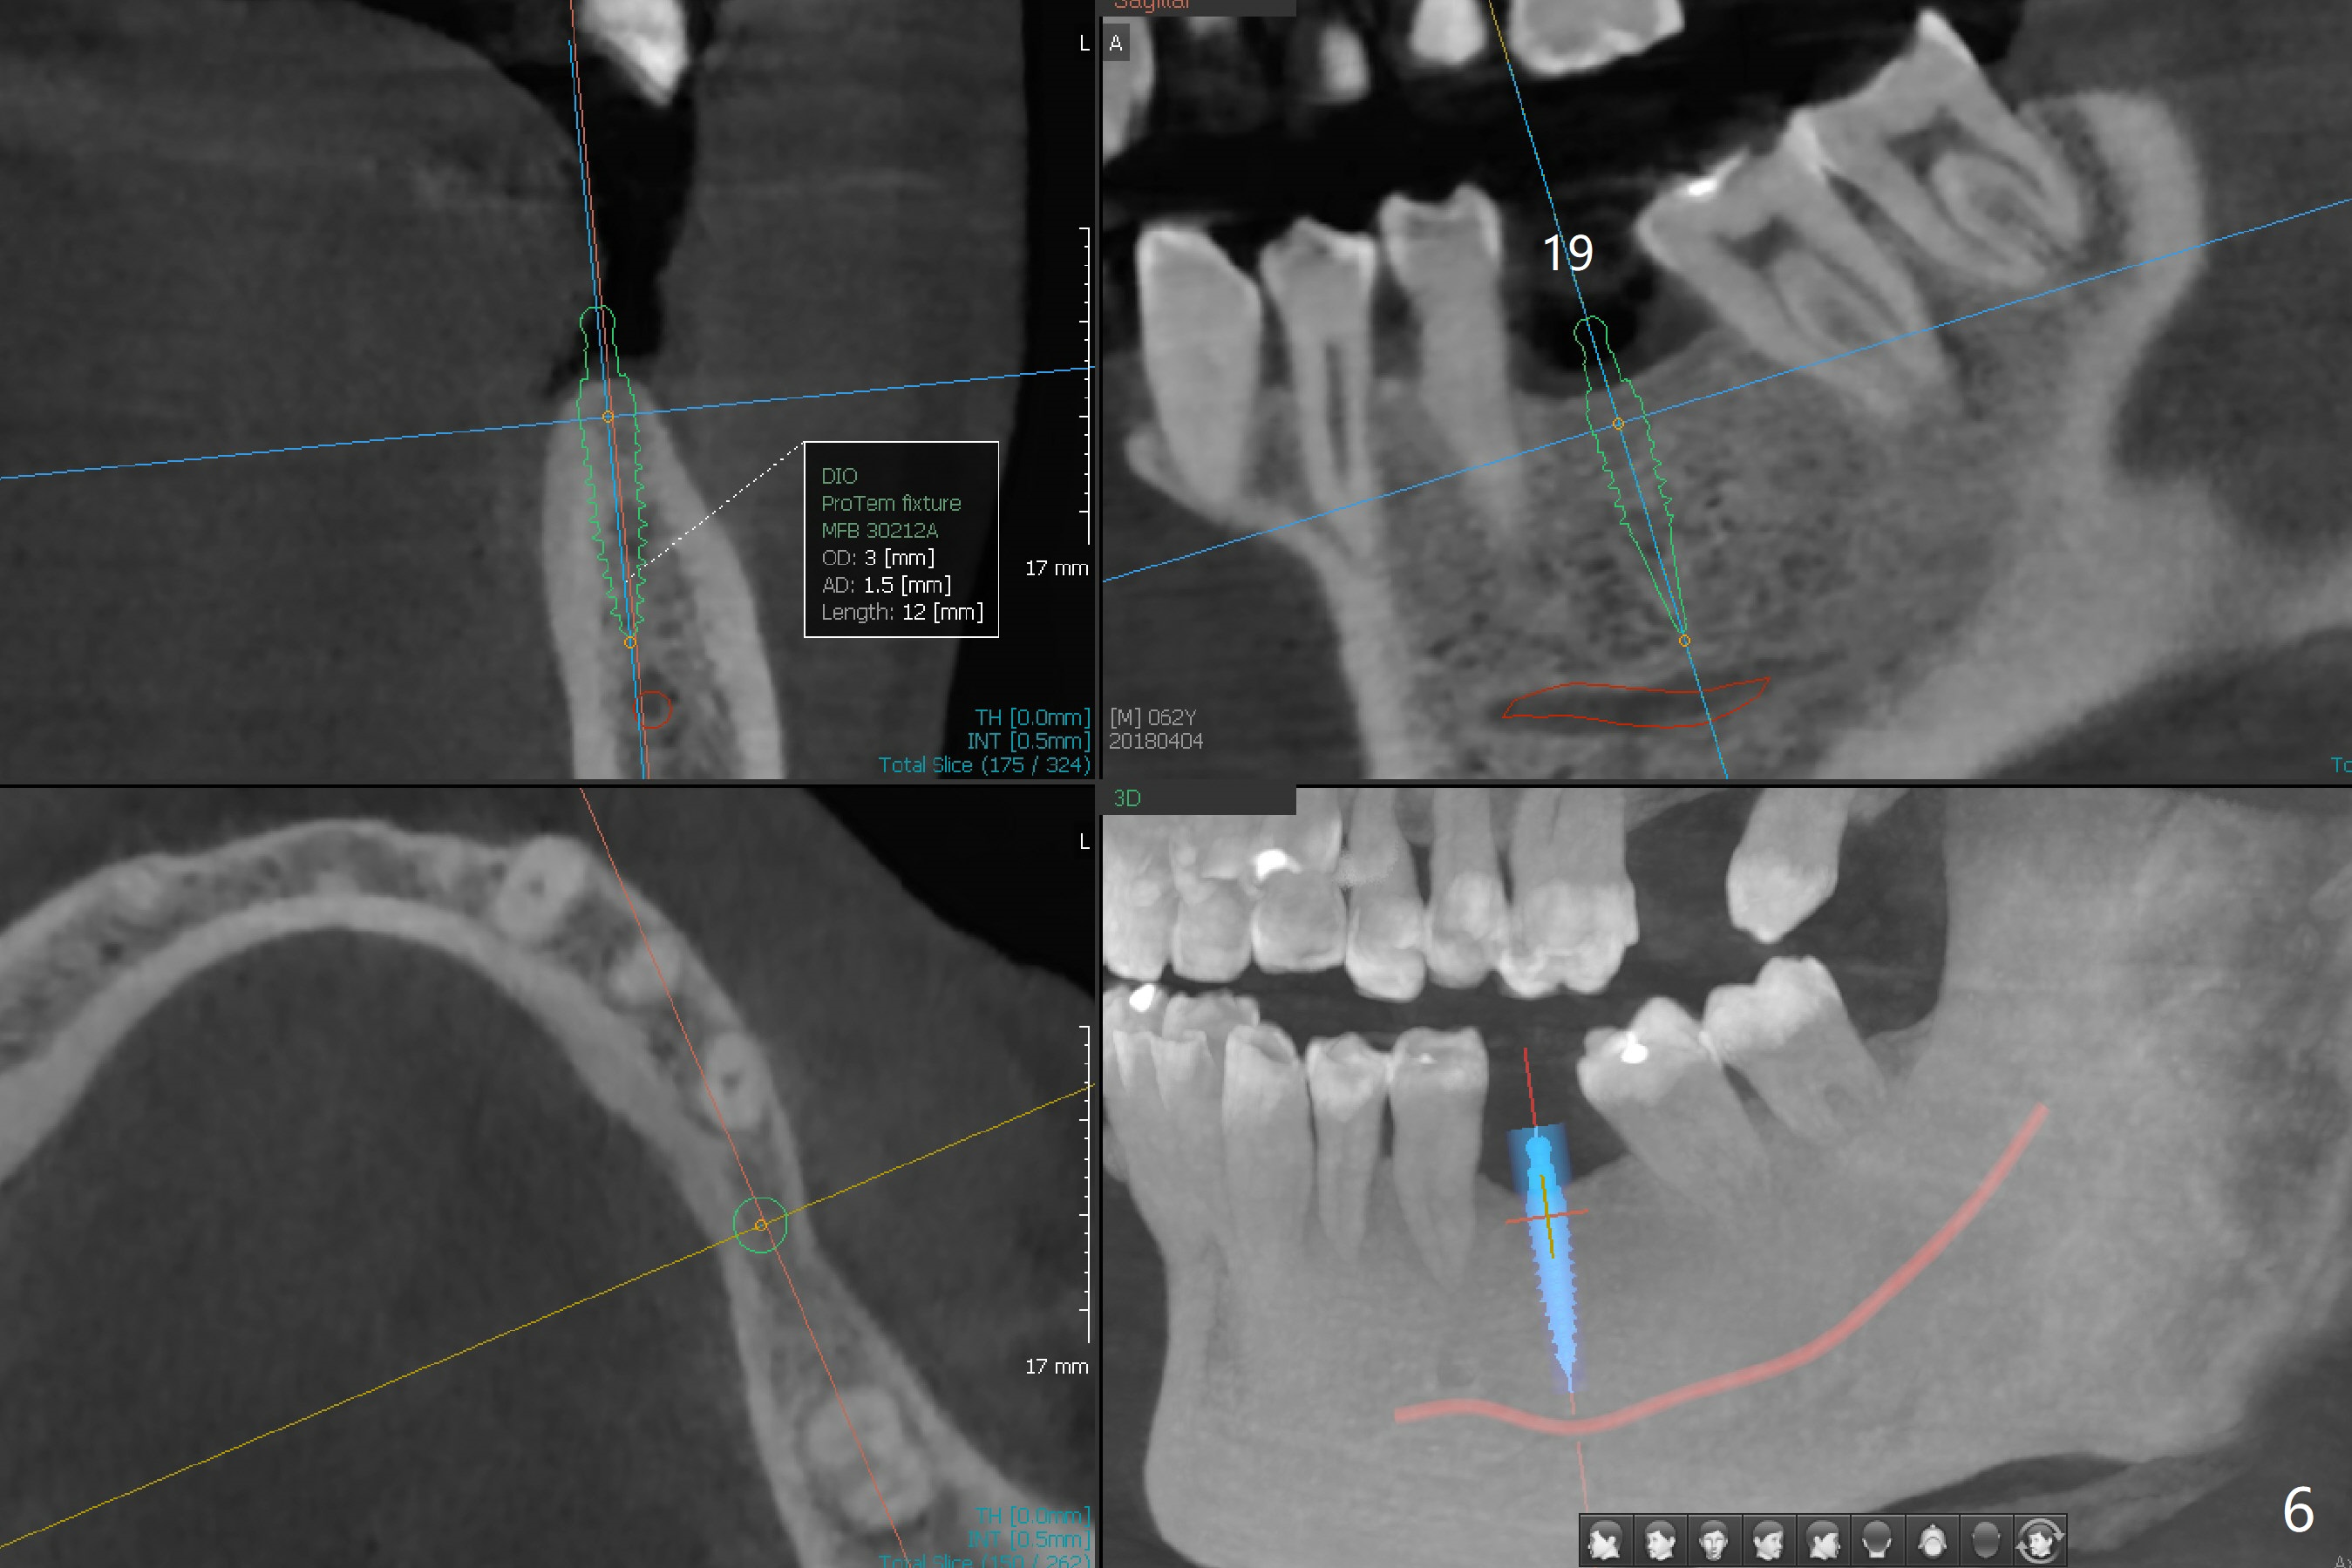

The patient would like to have implants to replace the lower RPD if the 1st surgery turns out to be successful. Due to the presence of the Mental Loop (Fig.1 red dashed line) and thin bone at #29 and 30 (Fig.3,4), 1-piece implants seem to be a good option. A 2-piece implant can be placed at #19 (Fig.5). After cementation of #15 implant crown, reanalysis of CT reveals that a 3x12 mm 1-piece implant is more appropriate at #19 with a space less than a premolar (Fig.6). With 2 of narrow short implants at #29 and 30, violation of the Mental Loop is less likely to happen than a single one in the middle of the edentulous area (Fig.7).